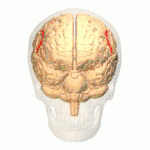

أسماء المناطق المبينة بالأرقام كما يلي:

1) القطب الجبهي ( Polus frontalis)

2) القطب القذالي ( Polus occipitalis )

3) الشق الطولاني للمخ ( Fissura longitudinalis cerebri)

4) التلفيف الجبهي العلوي ( Gyrus frontalis superior)

5) التلفيف الجبهي الوسطي ( Gyrus frontalis medius)

6) التلفيف الجبهي السفلي ( Gyrus frontalis inferior)

7) الثلم الجبهي العلوي ( Sulcus frontalis superior)

8) الثلم الجبهي السفلي ( Sulcus frontalis inferior)

9) الثلم أمام المركزي ( Sulcus praecentralis)

10) التلم المركزي ( Sulcus centralis)

11) الثلم خلف المركزي ( Sulcus postcentralis)

12) الثلم داخل الفص الجداري ( Sulcus intraparietalis)

13) الثلم الوحشي (شق سلفيوس) ( Sulcus lateralis (Fissura Sylvii))

14) التلفيف أمام المركزي ( Gyrus praecentralis)

15) التلفيف خلف المركزي ( Gyrus postcentralis)

16) الفصيص الجداري العلوي ( Lobulus parietalis superior)

17) الفصيص الجداري السفلي ( Lobulus parietalis inferior)

18) الفص القذالي ( Lobus occipitalis)

19) التلفيف الصدغي العلوي ( Gyrus temporalis superior)

20) التلفيف فوق الهامشي (؟) ( Gyrus supramarginalis)